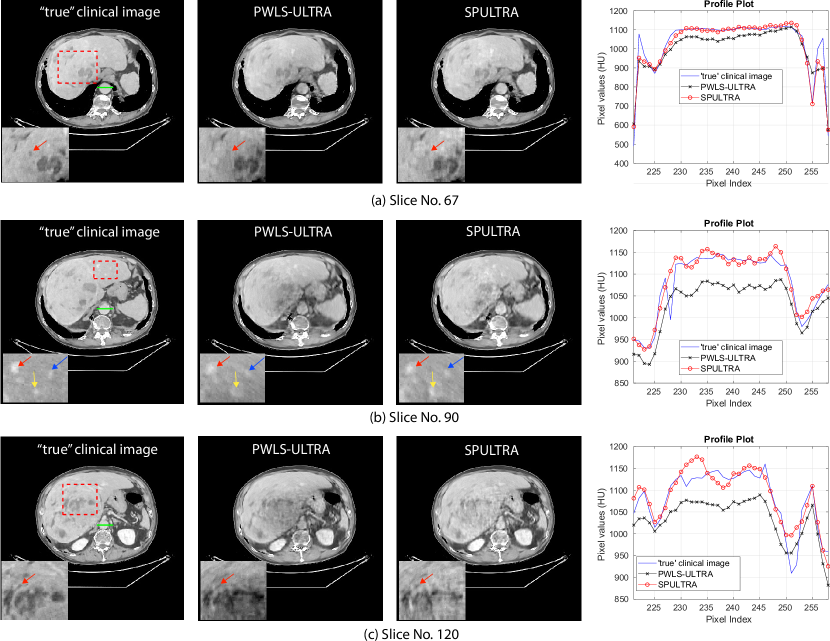

Fig. 4 shows the reconstructed images and the corresponding error images for PWLS-EP, PWLS-ULTRA, and SPULTRA, at and . Compared to the PWLS-EP result, both PWLS-ULTRA and SPULTRA achieved significant improvements in image quality in terms of sharper reconstructions of anatomical structures such as bones and soft tissues, and suppressing the noise. However, the PWLS-ULTRA method introduces bias in the reconstructions, which leads to larger reconstruction errors compared to the proposed SPULTRA method. In Fig. 4, we marked three 3D ROIs in the axial plane, i.e., ROI 1, ROI 2, and ROI 3. Fig. 5 shows the zoom-in images of a 3D plot of ROI 1, and those of ROI 2 and ROI 3 are shown in the supplement. We also plot the evolution of RMSE through the axial slices of the three 3D ROIs in Fig. 6. The figures demonstrate that SPULTRA clearly outperforms the competing PWLS-EP and PWLS-ULTRA schemes.

The above advantages of SPULTRA can be seen more clearly when observing the image profiles. Fig. 7 plots the image profiles for the three methods together with that of the ground-truth image. Fig. 4 shows the horizontal green solid line and the vertical red dashed line, whose intensities are plotted in Fig. 7. It is obvious that the profiles for SPULTRA are closest to the ground-truth among the three compared methods. The gap between the profiles of the PWLS-based methods and the ground-truth shows the bias caused by the compared PWLS methods.